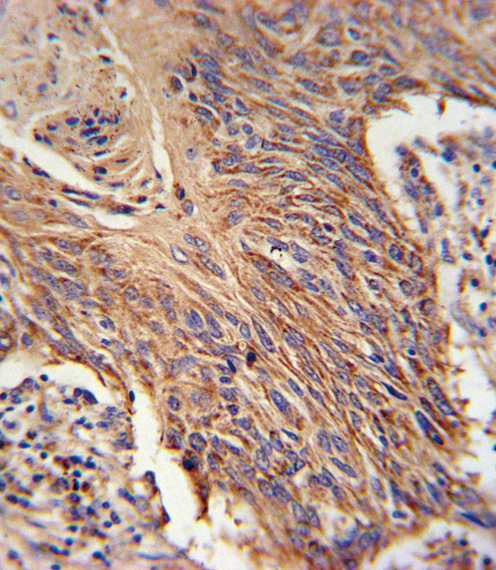

- Experimental details

- RDH10 Antibody immunohistochemistry of formalin-fixed and paraffin-embedded lung carcinoma followed by peroxidase-conjugated secondary antibody and DAB staining.